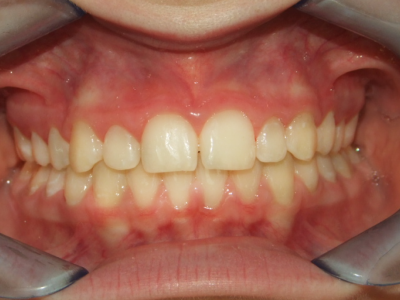

van 27.03-2014 tot 07.06.2016

Leeftijd bij aanvang: 9 jaar

1-6 Bonded Hyrax + volledig vast onderkaak & TransForce

7-13 Twin Block

14-26 volledig vast boven- en onderkaak + TPA

Leeftijd bij retentie: 11 jaar